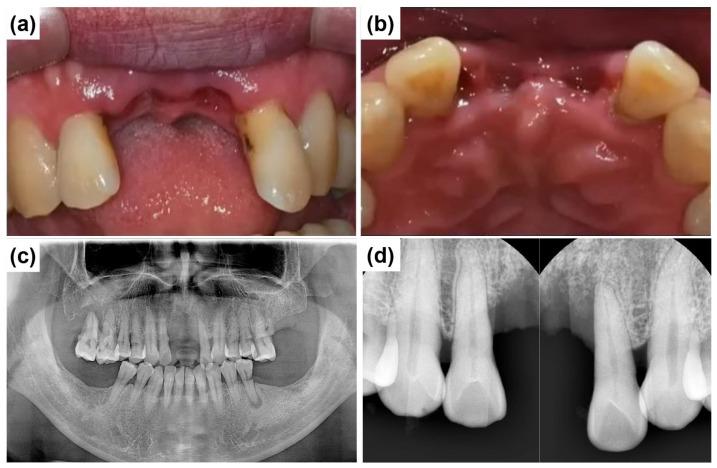

: The rehabilitation of severely resorbed anterior alveolar ridges presents significant clinical challenges due to esthetic demands and the limited bone volume in this region. Basal cortical implants, which are designed to engage dense basal bone, could offer an alternative by providing stable anchorage in compromised sites. : This report evaluates the ARi Implant System, which features cortical anchorage and a calcium-incorporated nanostructured surface (XPEED) in two anterior ridge defect cases. Soft tissue augmentation using a vascularized interpositional periosteal (VIP) flap was applied in one case, and biphasic calcium phosphate (BCP) grafting and collagen membranes were employed for ridge contouring in both cases. : At a two-year follow-up, both cases showed stable peri-implant tissues and satisfactory esthetic results. : Although basal cortical implants provide good primary stability, their use does not eliminate the need for bone augmentation, especially in the anterior esthetic region. Future clinical studies are required to substantiate long-term outcomes and broader applicability.

摘要

严重吸收的前牙牙槽嵴的修复由于美学需求和该区域有限的骨量而面临重大临床挑战。基底皮质种植体旨在与致密的基底骨结合,通过在受损部位提供稳定的锚固,可提供一种替代方案。:本报告评估了ARi种植系统,该系统在两个前牙嵴缺损病例中具有皮质锚固和含钙纳米结构表面(XPEED)。其中一例采用带血管蒂的间置骨膜(VIP)瓣进行软组织增量,两例均采用双相磷酸钙(BCP)移植和胶原膜进行嵴轮廓塑形。:在两年的随访中,两例均显示种植体周围组织稳定,美学效果满意。:尽管基底皮质种植体提供了良好的初期稳定性,但使用它们并不能消除骨增量的需求,尤其是在前牙美学区域。需要未来的临床研究来证实长期效果和更广泛的适用性。